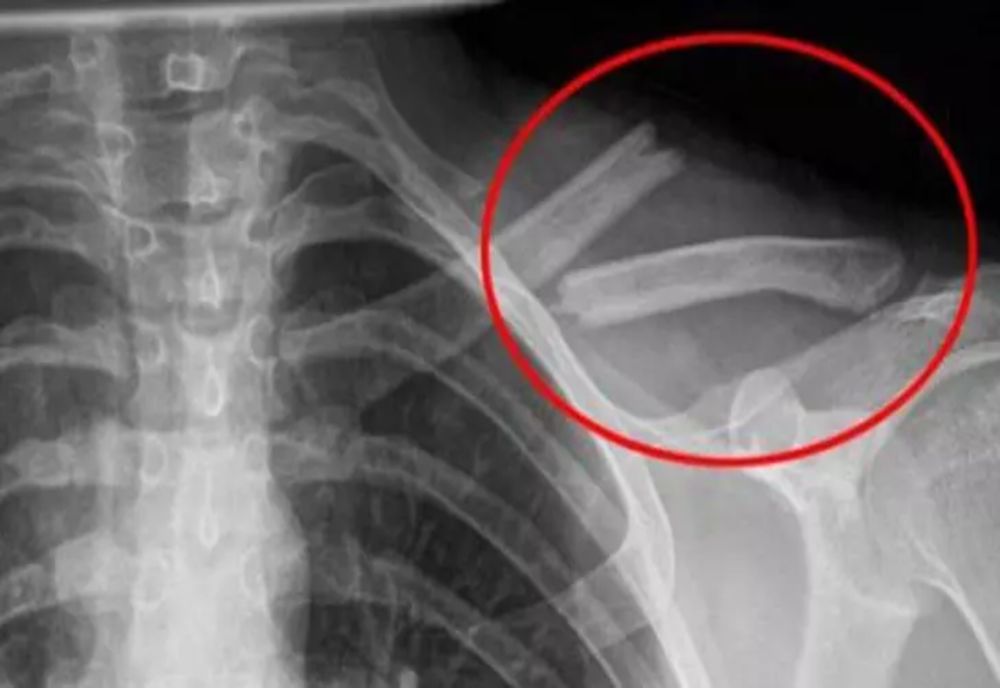

Articole cu eticheta "oase"